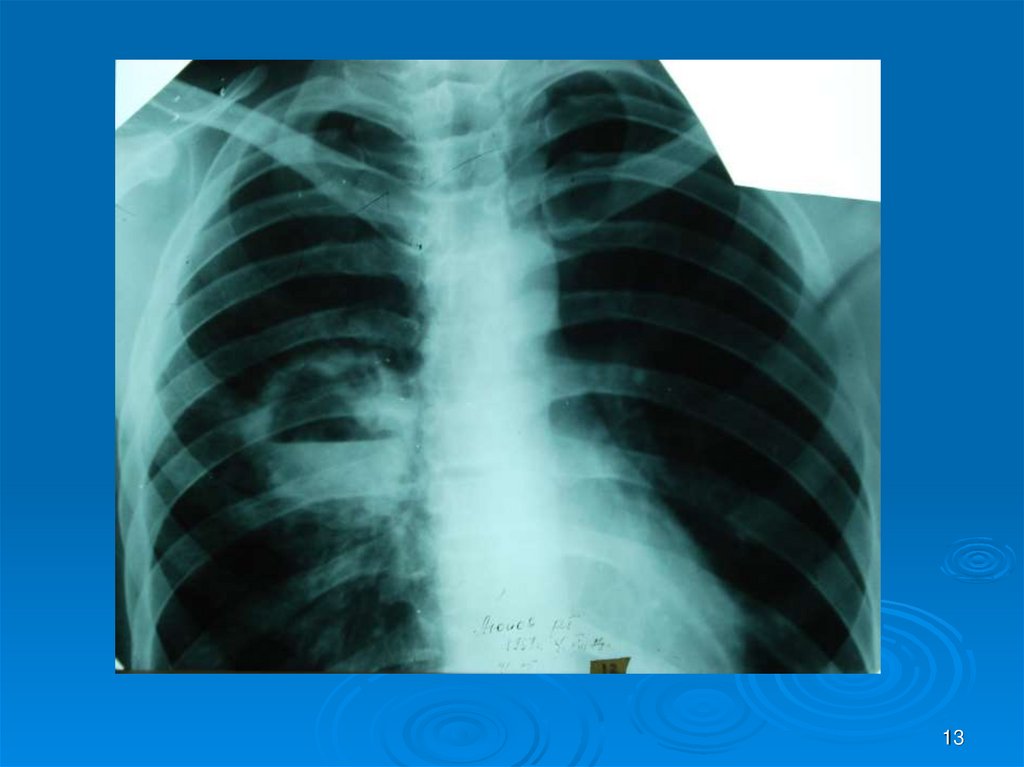

13.

13